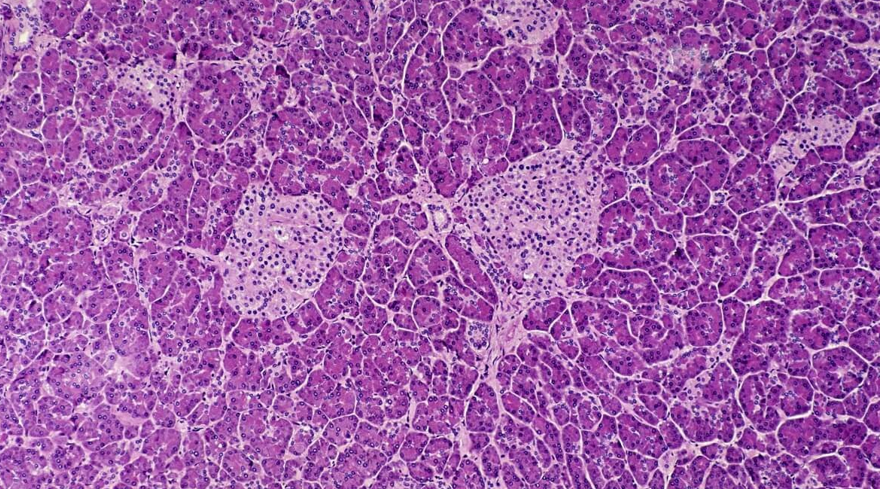

دانشمندان استرالیایی راهی برای فعال کردن مجدد سلولهای بنیادی پانکراس، به منظور بیان انسولین کشف کردهاند که درمانی جدید برای دیابت نوع ۱ است. این مطالعه با استفاده از دارویی انجام شده که توسط سازمان غذا و داروی آمریکا تأیید شده، اما در حال حاضر مجوزی برای درمان دیابت ندارد. اگرچه این تحقیق در مراحل اولیه است، ولی میتواند به درمانی در آینده منجر شود که در آن سلولهای نابالغ تولیدکنندهی انسولین (سلولهای بتا) جایگزین سلولهای تخریب شده در دیابت نوع ۱ شوند. دیابت نوع ۱ بیماری خود ایمنی است که در آن سلولهای بتا تولیدکننده انسولین در لوزالمعده، به طور انتخابی از بین میروند و مبتلایان به تزریق روزانه انسولین نیاز دارند. از طرفی تنها درمان مؤثر، پیوند جزایر پانکراس است که با وجود نتایج خوب برای افراد مبتلا به دیابت، به اهداکنندگان عضو وابسته است؛ بنابراین استفادهی گسترده از آن محدود شده است. سلولهای پیشساز پانکراس، سلولهای بنیادی هستند که توانایی تمایز به سلولهای مختلف پانکراس، از جمله سلولهای بتا را دارند. برنامهریزی مجدد این سلولهای بنیادی به سلولهای بتا تولیدکننده انسولین و پیوند مجدد آنها در لوزالمعده، قبلاً بهعنوان یک درمان جایگزین برای دیابت نوع ۱ پیشنهاد شده بود اما بحثبرانگیز باقی مانده است. برای بررسی این روش، این تیم سلولهای بنیادی پانکراس را از یک اهداکننده دیابتی نوع ۱و همچنین از دو اهداکننده غیردیابتی، جمعآوری کرده و آنها را با GSK126 درمان کردند. GSK126 فعالیت یک آنزیم کلیدی به نام EZH2 متیل ترانسفراز را مهار میکند. این آنزیم بیان ژنهایی را مهار میکند که منجر به تمایز پیشساز به سلولهای بتا میشوند. با درمان سلولها با GSK126، آنها بیان این ژنها و مهمتر از همه بیان ژن انسولین را در سلولهای پیشساز از اهداکنندگان غیردیابتی و دیابتی نوع 1 بازسازی کردند. در هر صورت مشخص نیست که این نتایج در همه شرایط قابل تعمیم باشد؛ زیرا آزمایشها شامل سلولهای پانکراس یک کودک دیابتی نوع ۱ میشد و مشخص نیست که در دیابت طولانیمدت، ترمیم ژنهای پیشساز سلول بتا رخ دهد. به هر حال این نتایج نشاندهنده گام مهمی در مسیر درمانی پایدار است که ممکن است درمانی برای انواع دیابت باشد. :منبع